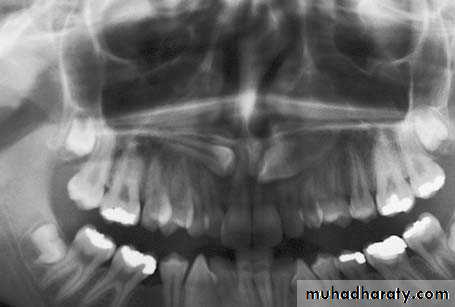

Radiograph showing impacted maxillary canines. Right canine is located labially while left canine is located palatally